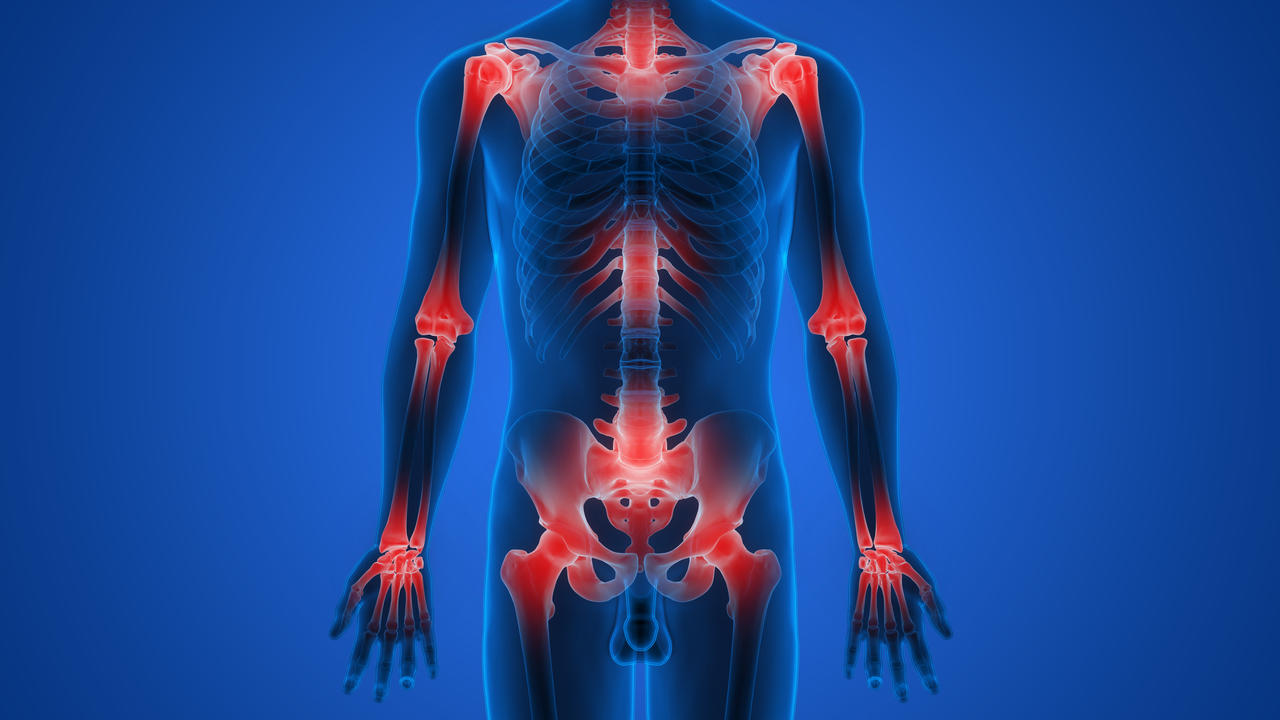

I distretti corporei maggiormente coinvolti sono: anche, colonna vertebrale, polsi, spalle e femore. Da notare che una frattura al femore, può condurre il soggetto colpito a una condizione di disabilità fisica.

Le sue conseguenze sono una diminuzione della densità minerale ossea e un aumento della fragilità e debolezza dell’apparato scheletrico con predisposizione alla comparsa di fratture al collo del femore, al femore, ai corpi vertebrali, all’avambraccio e alla parte prossimale vicino alla spalla per quanto concerne la frattura dell’omero.

Dove si riscontrano le fratture da osteoporosi

In tutto lo scheletro si possono riscontrare fratture da osteoporosi, ma quelle più frequenti sono:

- all’estremità prossimale del femore, in zona inguinale;

- all’estremità distale del radio, cioè al polso;

- sulle vertebre, lungo la colonna dorso lombare;

- all’estremità prossimale dell’omero, in zona ascellare;

- alle anche, intorno al bacino.